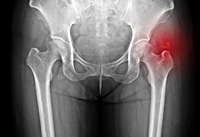

7. 고관절 골절

골밀도가 낮아지는 60대에 주로 발생하며, 고관절 골절 후에는 삶의 질이 크게 저하됩니다. 사망률도 높아져 심각한 질환입니다.